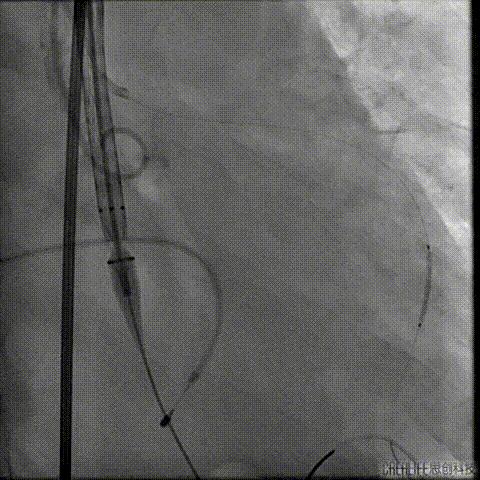

行急诊手术 腹主动脉及左侧股动脉造影

左侧股动脉见造影剂外渗

球囊压迫后植入覆膜支架

复查造影